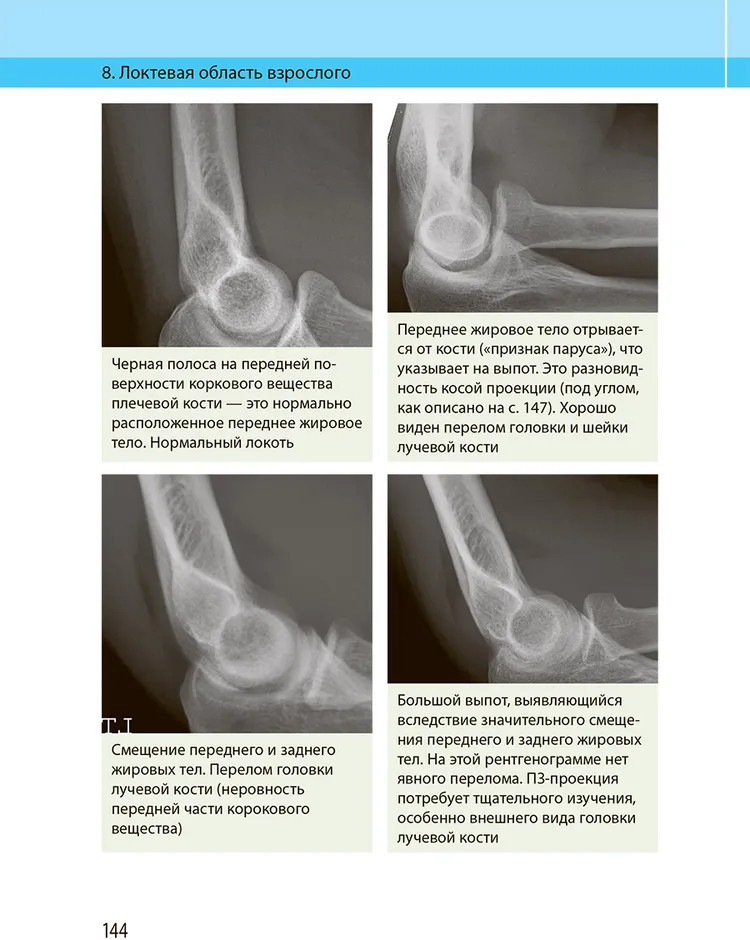

💳 Оплатить за товар можно при получении 🇰🇿 Есть бесплатная доставка по Казахстану от 1 дня 🎁 Копите бонусы с каждой покупки Авторы данной книги — опытные и высококвалифицированные врачи. В руководстве достаточно полно изложена нормальная рентгеноанатомия, описаны особенности укладок, используемых при рентгенографии различных органов. В каждой главе представлено сравнение травматических изменений с другими патологическими процессами и вариантами развития, прежде всего в тех типичных случаях, в которых врачи, анализирующие рентгенограммы, наиболее часто сталкиваются с дифференциально-диагностическими трудностями. Приведена рентгеносемиотика повреждений различных органов, включая повреждения, характерные для детского возраста. |